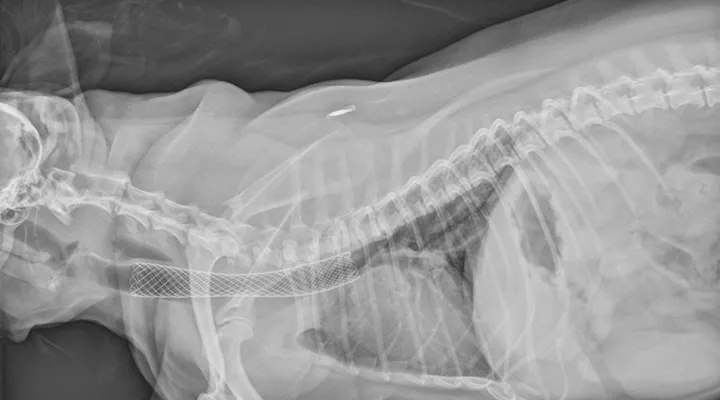

An 8-year-old neutered male Yorkshire terrier is presented for respiratory distress. The patient had been exhibiting a loud, progressive, honking cough for 18 months before presentation. The owners had attempted nebulization and coupage at home without improvement. Physical examination reveals a distressed patient with a respiratory rate of 60 breaths/min, loud upper airway stridor and stertor, and coughing. Temperature is 103.9F (39.9C), heart rate is 160 bpm, and mucous membranes are a muddy/cyanotic color. Oxygen is administered, and the patient improves enough for lateral radiography; radiographs reveal a grade III to IV tracheal collapse at the thoracic inlet and a mild interstitial pattern, most prominent in the caudodorsal region of the lungs (Figure 1).

Radiograph showing grade III to grade IV tracheal collapse and a mild interstitial pattern